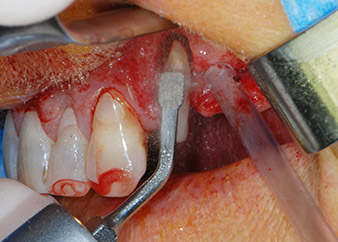

One month later, on the day of surgery, pain and inflammation at tooth 24 were minimal, but mobility of Miller class 2 was still present. After opening the flaps and cleaning the periapical and peri radicular infected tissue, the extent of the bone defect became obvious (Figs. 2 and 3).

total loss of bone and attachment

Fig. 2 and 3: After raising flaps, one month after endodontic revision and initiation of full-mouth periodontal therapy, the buccal root of tooth 24 showed a total loss of bone and attachment.

However, we maintained our initial plan to retain both teeth as temporary bridge abutments during the six-months osseointegration period of the implants. At reentry, the situation would have to be reassessed. First, in an attempt to manage the endo-perio problem, the remaining root surface was carefully debrided with piezoelectric equipment (Piezomed, W&H, used with the spatula-shaped insert S1, originally designed for erosion of the lateral sinus wall) (Fig. 4).